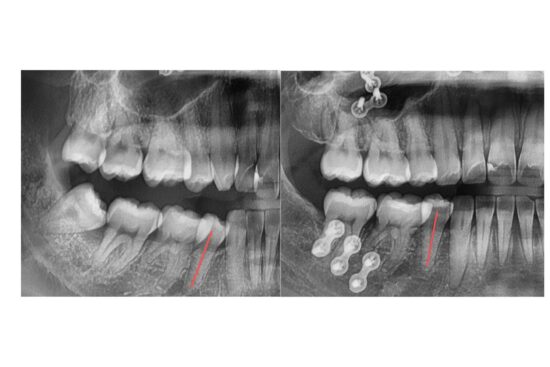

アタッチメントがないとどうなる?

アタッチメントなしでマウスピース矯正を行うことも可能ですが、

その場合、歯根のコントロールが不十分になる可能性があります。

歯根の動きをしっかりコントロールするためには、アタッチメントが必須です。

つまり、アタッチメントがあるからこそ、歯根を正しく動かすことができ、より確実に治療が進められるのです。